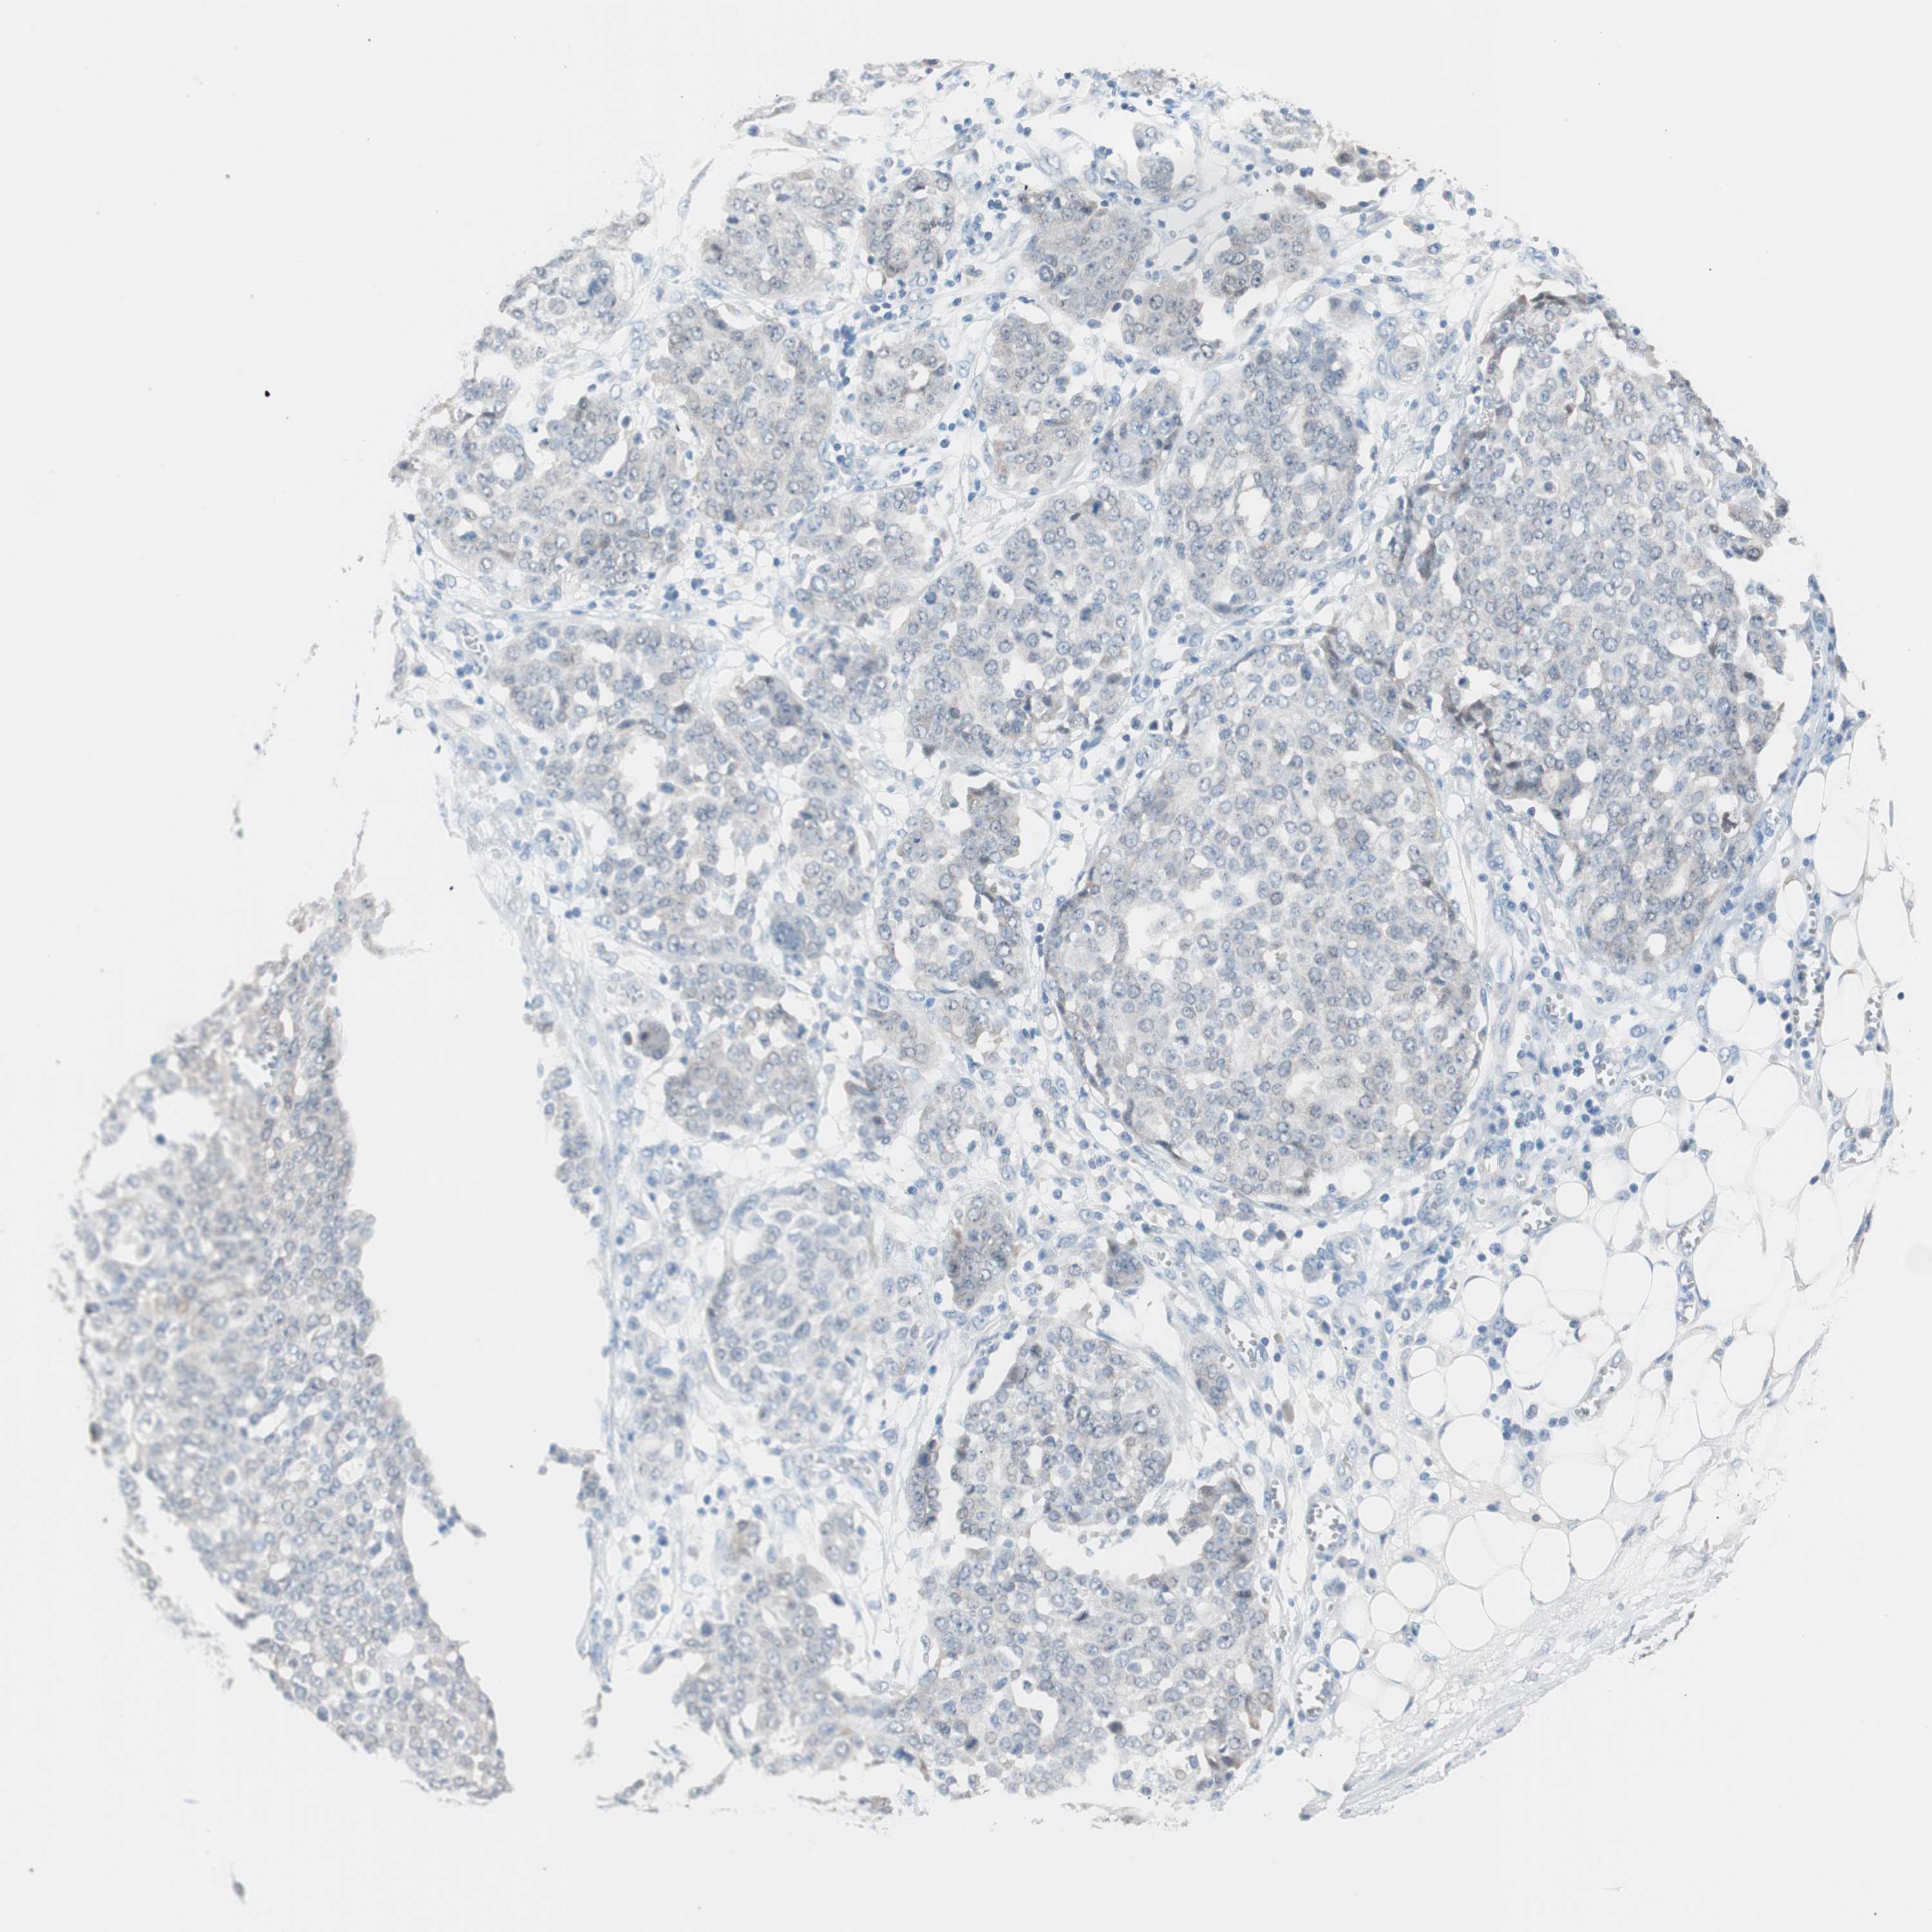

OVARIAN CANCER - Protein expressioni

A mouse-over function shows sample information and annotation data. Click on an image to view it in a full screen mode. Samples can be filtered based on level of antibody staining by selecting one or several of the following categories: high, medium, low and not detected. The assay and annotation is described here.

Note that samples used for immunohistochemistry by the Human Protein Atlas do not correspond to samples in the TCGA dataset.

Antibody stainingi

Antibody staining in the annotated cell types in the current human tissue is reported as not detected, low, medium, or high, based on conventional immunohistochemistry profiling in selected tissues. This score is based on the combination of the staining intensity and fraction of stained cells.

Each image is clickable and will lead to virtual microscopy that enables deeper exploration of all samples and also displays staining intensity scores, fraction scores and subcellular localization as well as patient and tissue information for each sample.

Antibody HPA006884

Antibody CAB002452

Staining

High

Medium

Low

Not detected

Cystadenocarcinoma, serous, NOS

Carcinoma, NOS

Cystadenocarcinoma, mucinous, NOS